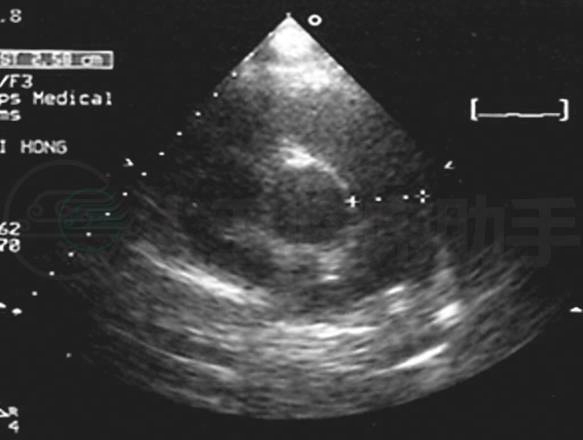

入院前门诊超声心动图(图3):左心室舒张末期前后径36mm,射血分数78%,右心室前后径40mm,右心房、右心室扩大,右心室壁增厚,运动正常,左心室内径大致正常。室间隔左移,左心室呈“D”字形,房、室间隔完整。室壁厚度正常,室间隔运动异常。肺动脉明显扩张,腔内未见明显异常回声。三尖瓣环扩张,致瓣叶对合不拢。余瓣膜形态、结构启闭未见明显异常。三尖瓣少量高速反流,肺动脉瓣少~中量高速反流,估测肺动脉收缩压84mmHg。

图3 入院前门诊超声心动图:右心扩大,肺动脉高压